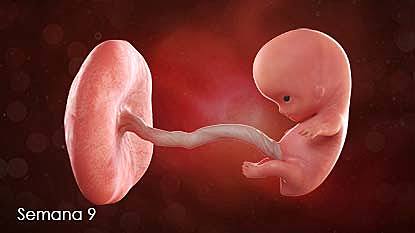

• Semana 9

Semana 9

-Se forman los pezones y folículos pilosos.

-Los codos y los dedos de los pies son visibles.

-Todos los órganos esenciales se comienzan a formar

-Los párpados están más desarrollados.

-Las características externas del oído comienzan a tomar su forma final.

-Continúa el desarrollo de las características faciales.

-Los intestinos rotan.

-Tiene el tamaño de una uva, unos dos centímetros y medio.

-La cola al final de la espalda desaparece.

-El embrión puede moverse de forma involuntaria.